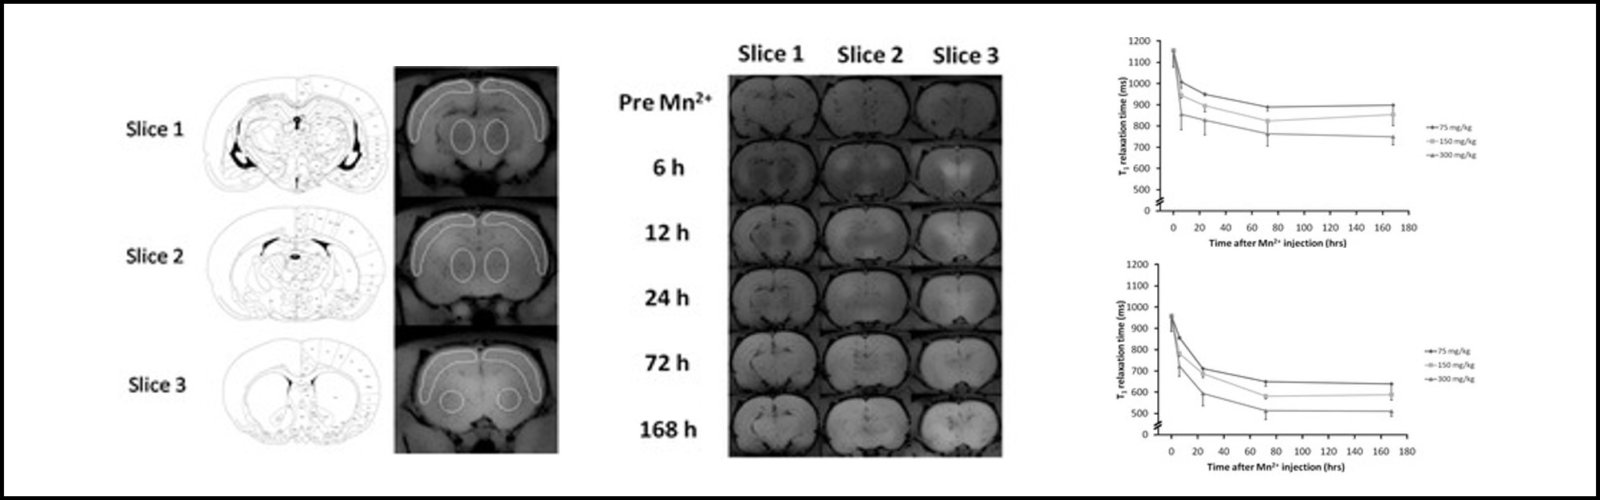

To provide image processing and analysis service to help scientists and clinicians develop imaging biomarkers using different imaging modalities with the goal of:

• Detecting and diagnosing diseases to enable an early stage to enable early treatment intervention.

• Tracking disease progression/tissue regeneration allowing clinicians to evaluate the medical condition.

• Monitoring treatment effects either via conduits for drug delivery and regenerative medicine applications or via other interventional procedures to facilitate therapeutic mechanisms.